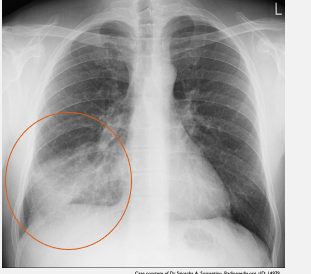

What does this CXR indicate? - Pneumoperitoneum - Pneumothorax - Pulmonary oedema - Consolidation - Pleural effusion

What does this CXR indicate? - **Pneumoperitoneum** : **Gas is beneath both hemidiaphragms, more prominent on the right, in keeping with a pneumoperitoneum. Sternotomy wires** - Pneumothorax - Pulmonary oedema - Consolidation - Pleural effusion